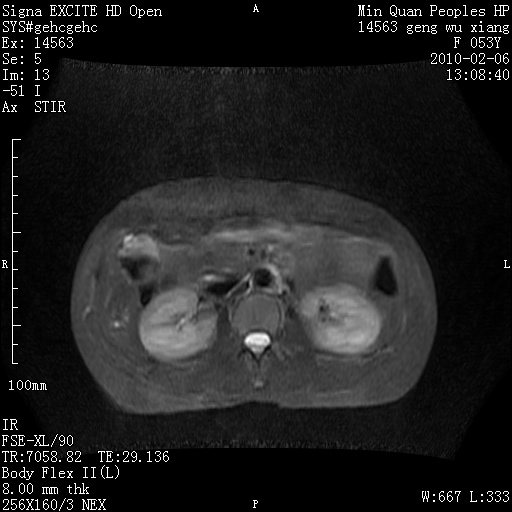

标题: MRI2762:胆道梗阻原因?

f,53y,全身黄染多日。

高位胆道梗阻 胆管癌可能性大

支持 高位胆道梗阻 胆管癌可能性大。